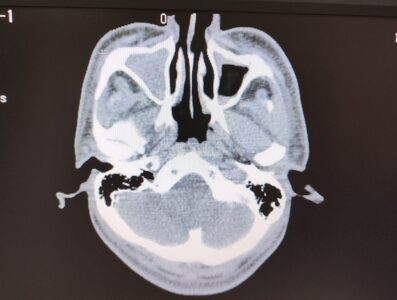

いきなりですが実は私、結構重症な副鼻腔炎だったんです。

画像でいう左側、三角のグレーの部分が膿で充満しているのがわかると思います。

副鼻腔炎、簡単に言えば鼻の奥の空洞に膿が溜まり炎症を起こし、それにより頭痛とか発熱などいろんな症状が起きる病気です。

詳細は省きますが、勤務先の外来→近隣の内科クリニック→かかりつけの耳鼻科→総合病院→かかりつけの歯科→総合病院……と、あちこち回って「両側上顎洞炎、篩骨洞炎」と確定、